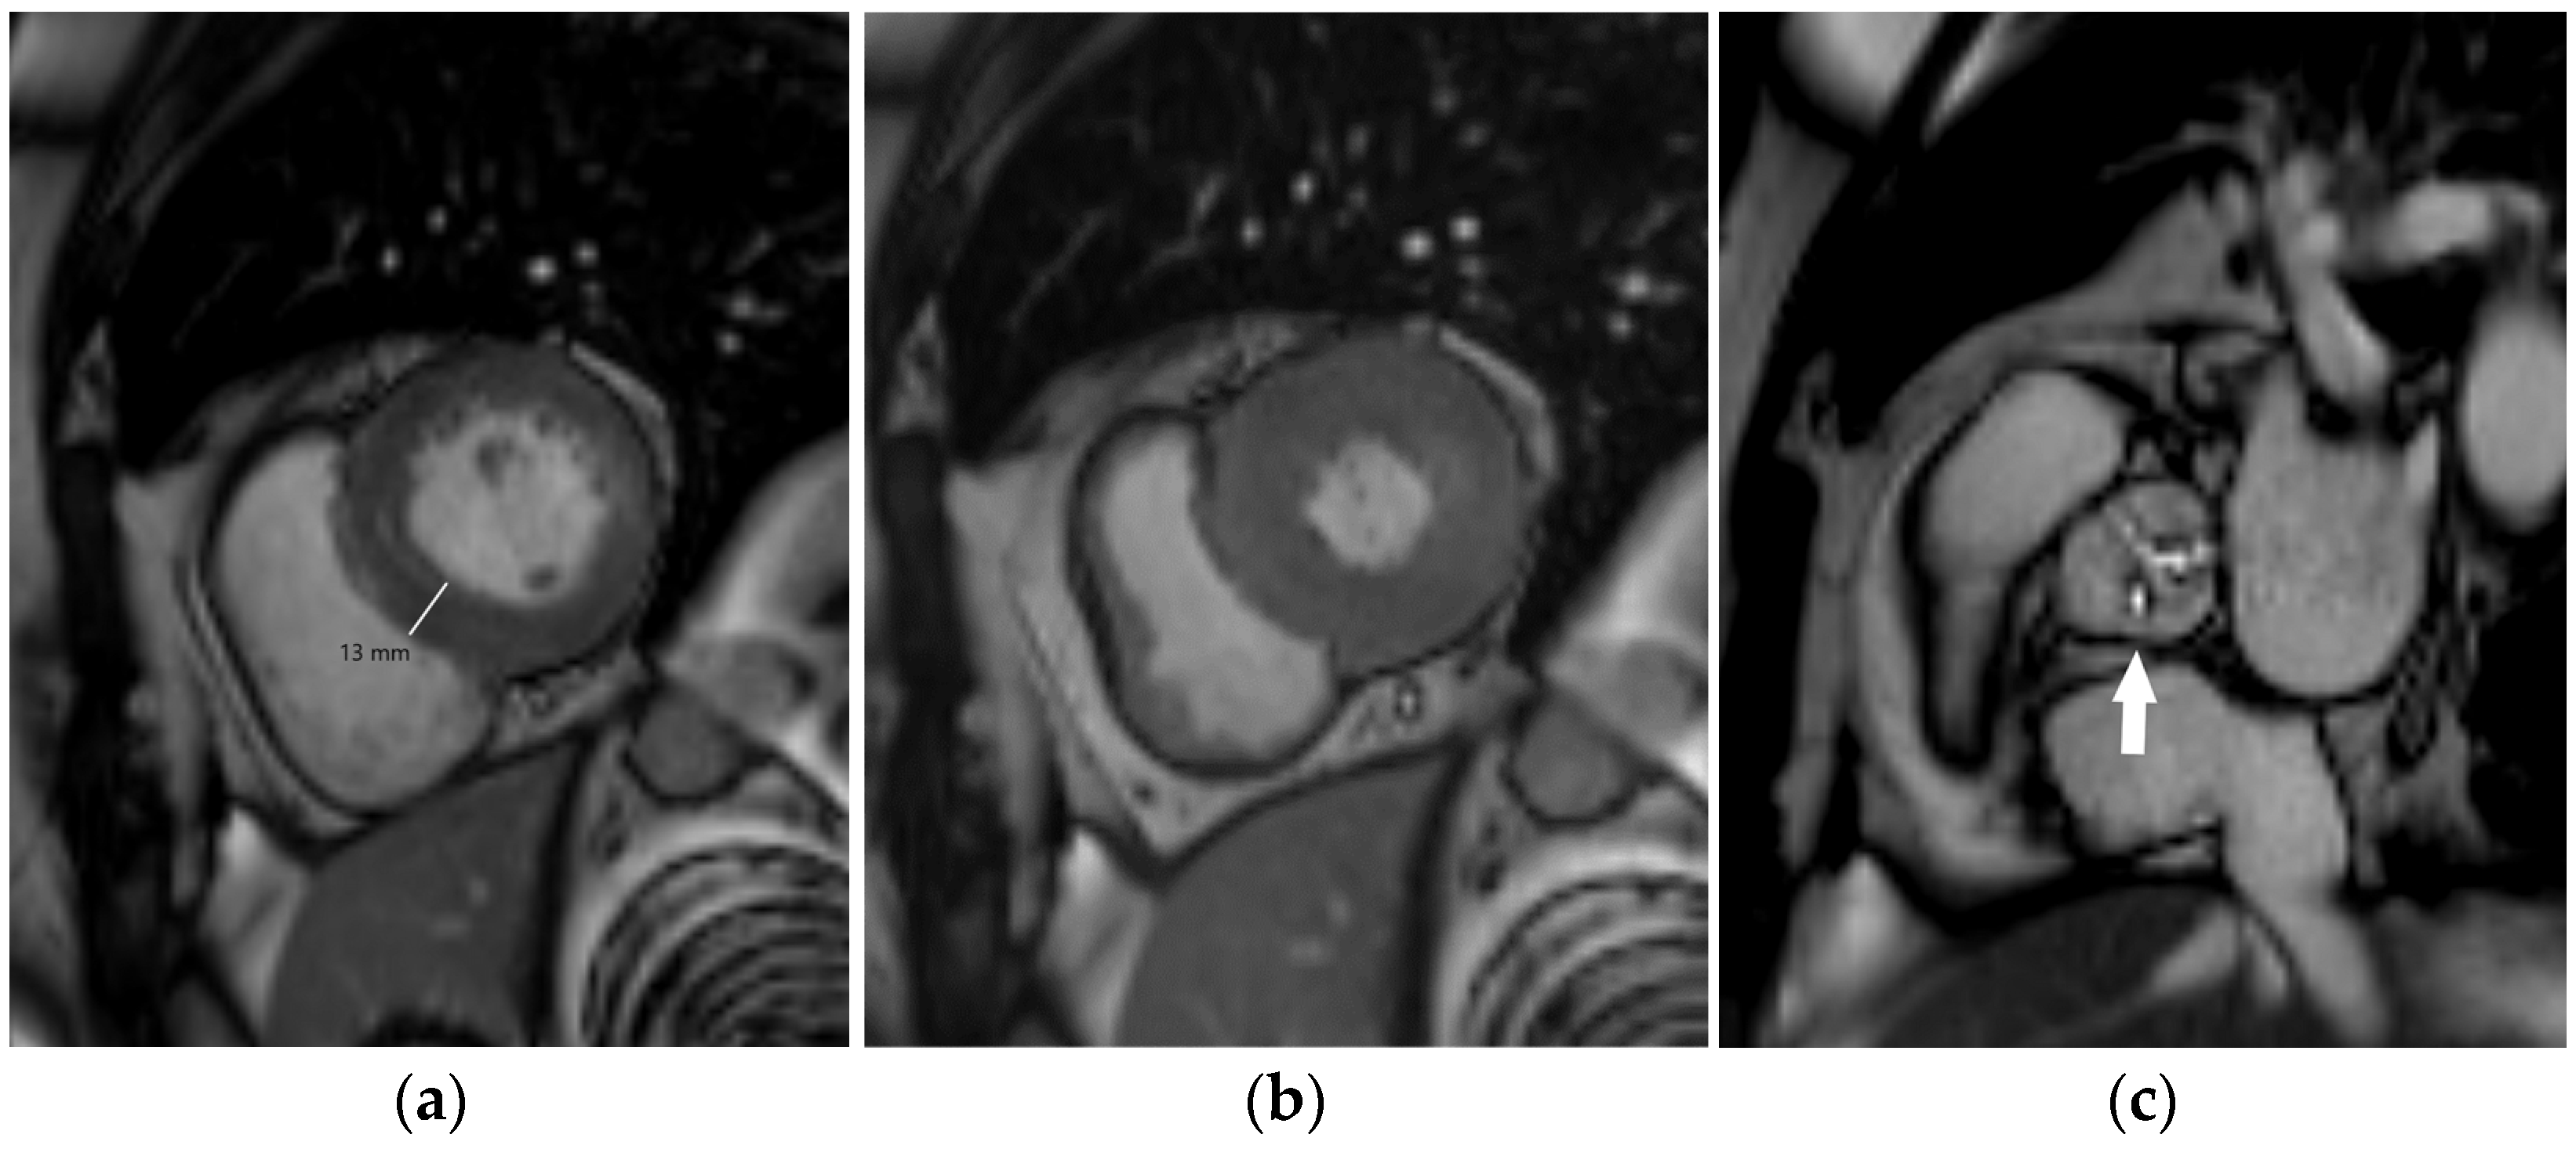

Left ventricular hypertrophy is an adaptive remodeling process aiming to reduce LV wall stress as a response to pressure overload caused by increased arterial stiffness, systemic hypertension, or aortic stenosis. LV hypertrophy is asymptomatic for many years, but over time, the adaptive process becomes maladaptive, with an increasing risk of developing cardiovascular diseases including coronary artery disease, sudden death, and heart failure (HF). LV hypertrophy can be detected electrocardiographically, but echocardiography and MRI are more sensitive methods that also enable quantification of the LV mass (Figure 2). LV hypertrophy is considered to be target-organ damage in a hypertensive population [27], and regression of LV hypertrophy is advised as a surrogate endpoint in the treatment of hypertensive heart disease [34].

Figure 2.

Cardiac MRI showing concentric left ventricular hypertrophy in an 80-year-old male patient with severe aortic stenosis. End-diastolic (a) and end-systolic (b) short-axis steady-state free precession (SSFP) images representing increased myocardial thickness (13 mm in end-diastole). SSFP image parallel to the aortic valve plane showing its impaired systolic opening (arrow, (c)).